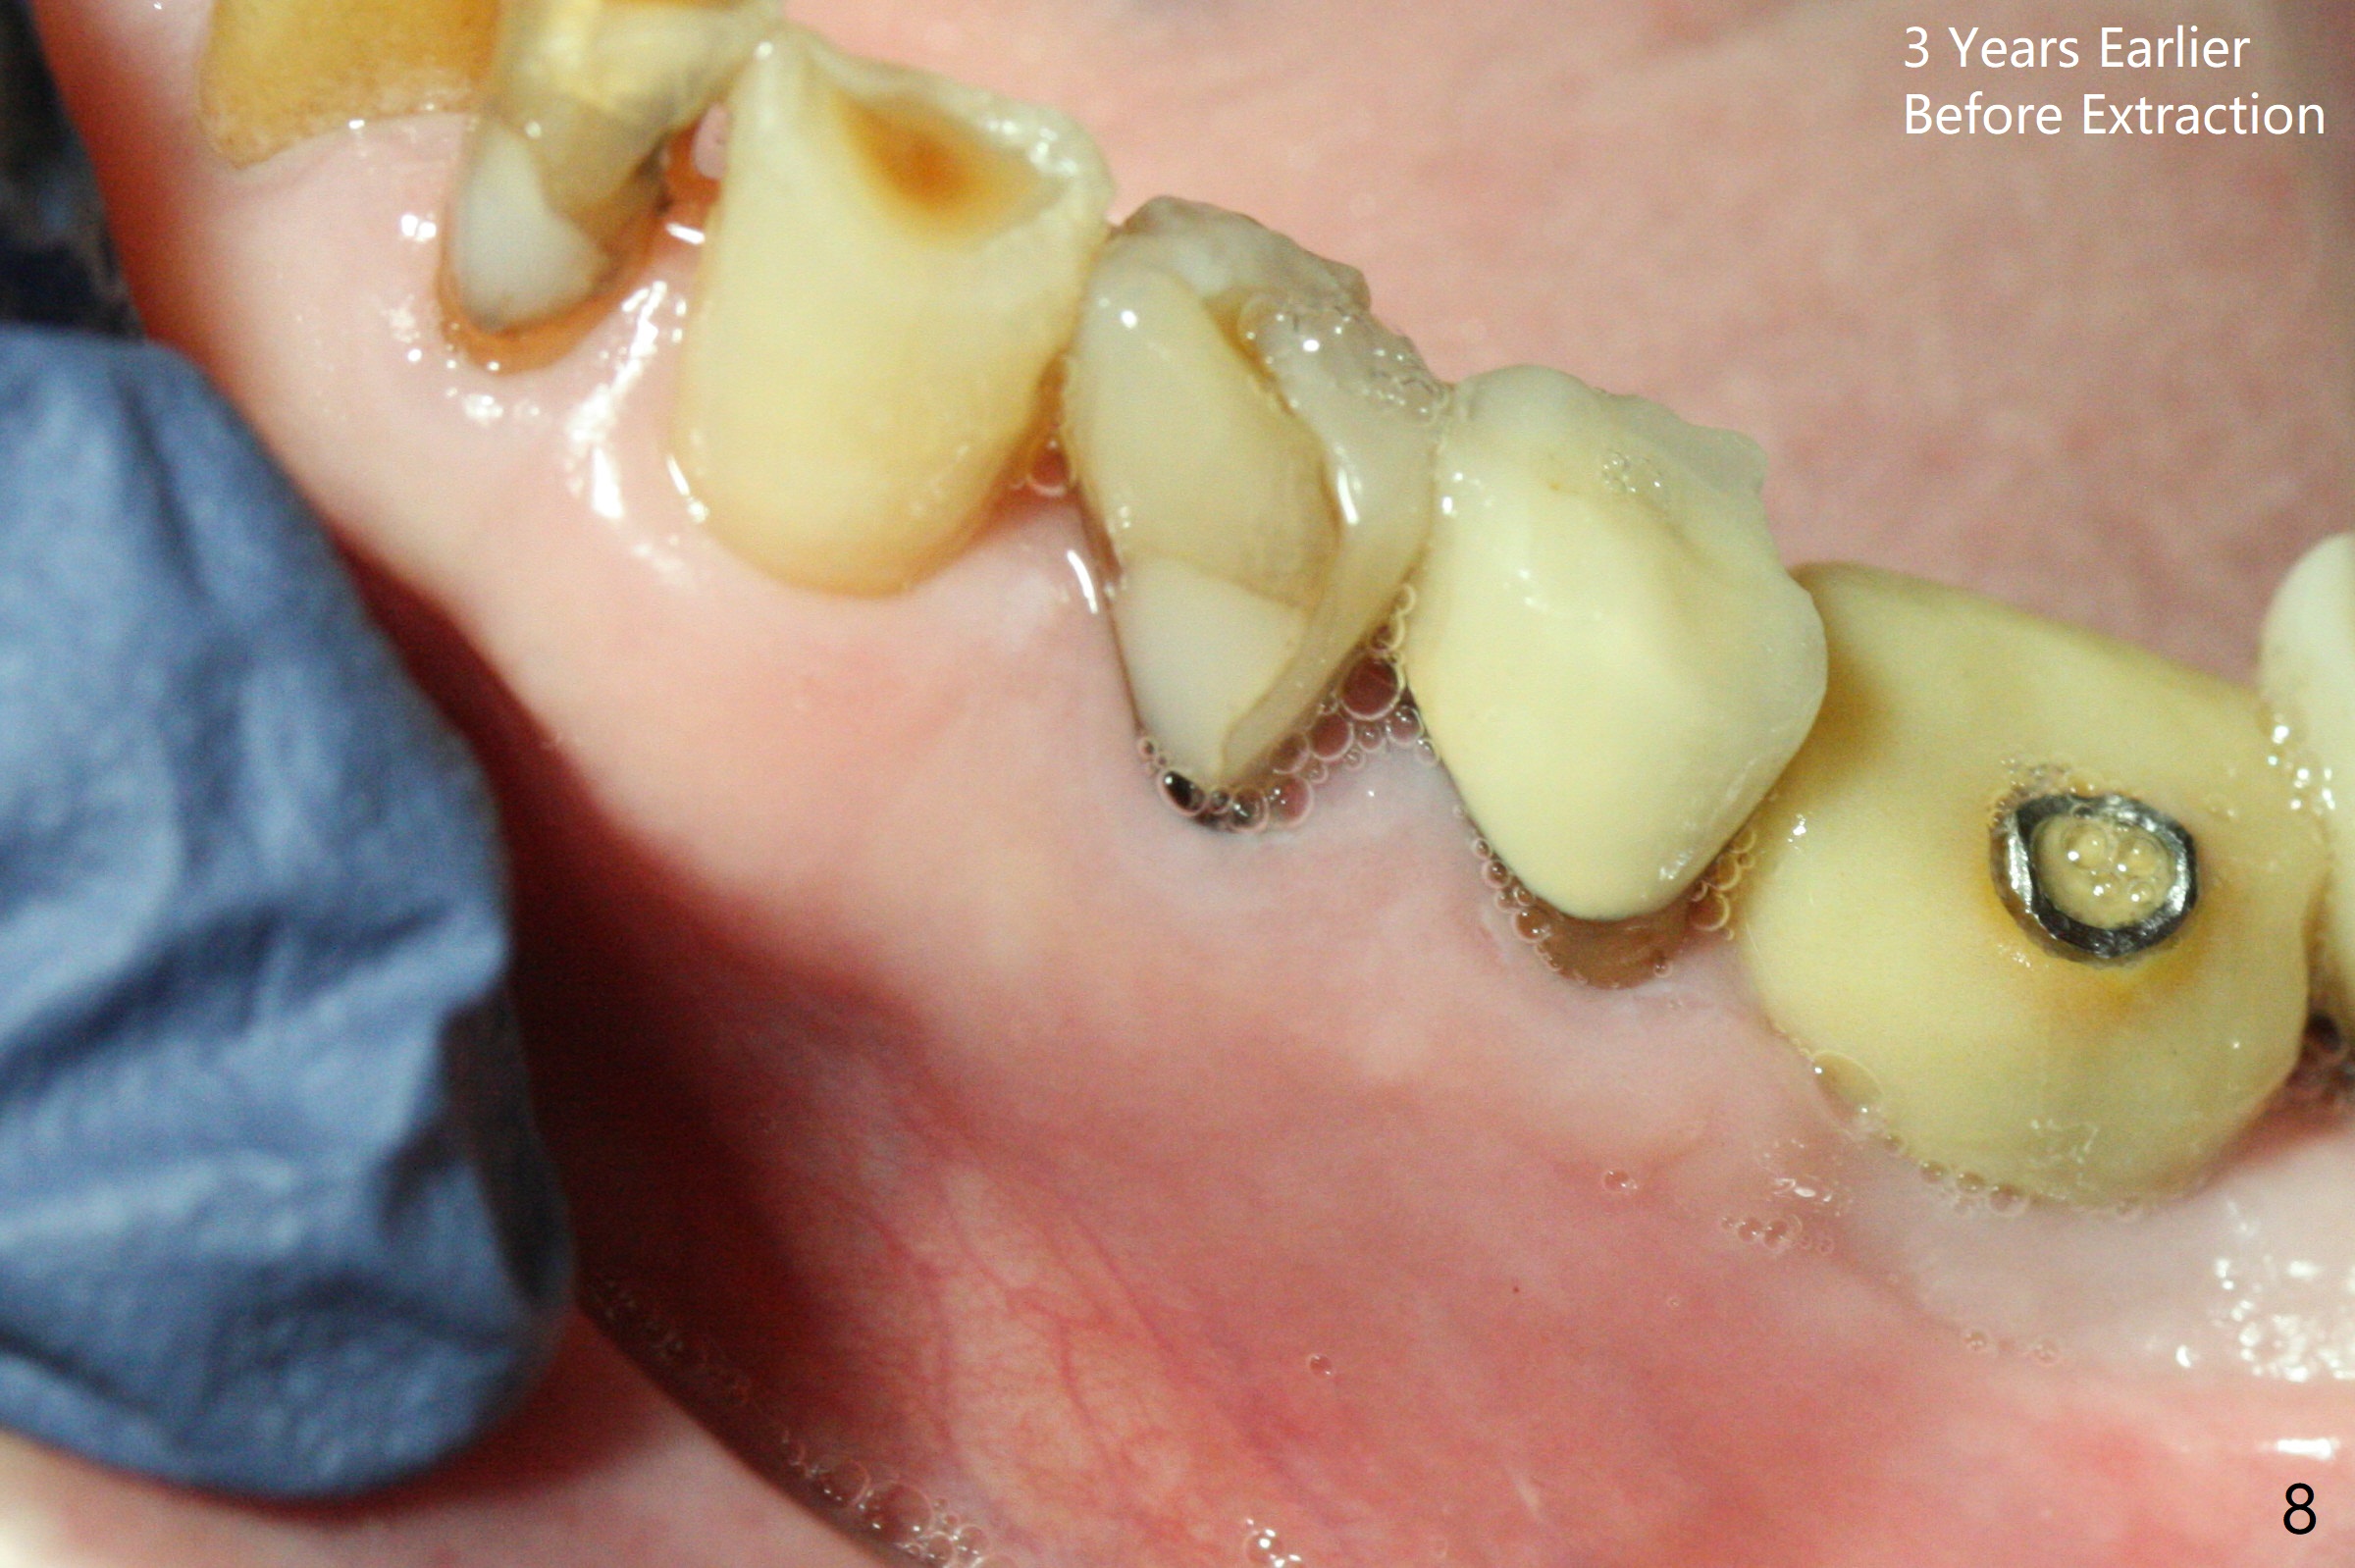

Extraction of the fractured tooth at #21 is as difficult as #19 (requiring incision). Because of the long root and hemorrhage, the apex of the tooth (Fig.1 black *) and a thin layer of the buccal shield (white *) remain when osteotomy is initiated. Due to hard bone, a 3.8x11.5 mm implant achieves insertion torque of ~35 Ncm (Fig.2); with placement of a 4.5x4(3) mm abutment, an immediate provisional is fabricated. There is limited remaining space for bone graft. The patient will return for final restoration 4 months postop; the buccal plate will be expected to have not collapsed! The implant seems to be osteointegrated, while the root piece (socket shield *) is exposed 4 months postop (Fig.3). The socket shield seems to be harmless, difficult to trim without local anesthesia and associated with no buccal plate concavity (Fig.4,5 <). With socket shield at #21, the crown looks normal, whereas the one at #19 without socket shield looks long, suggesting vertical bone loss early postop (before restoration, Fig.6).没有牙根处,角化龈少(图七,与术前(图八)对比)。